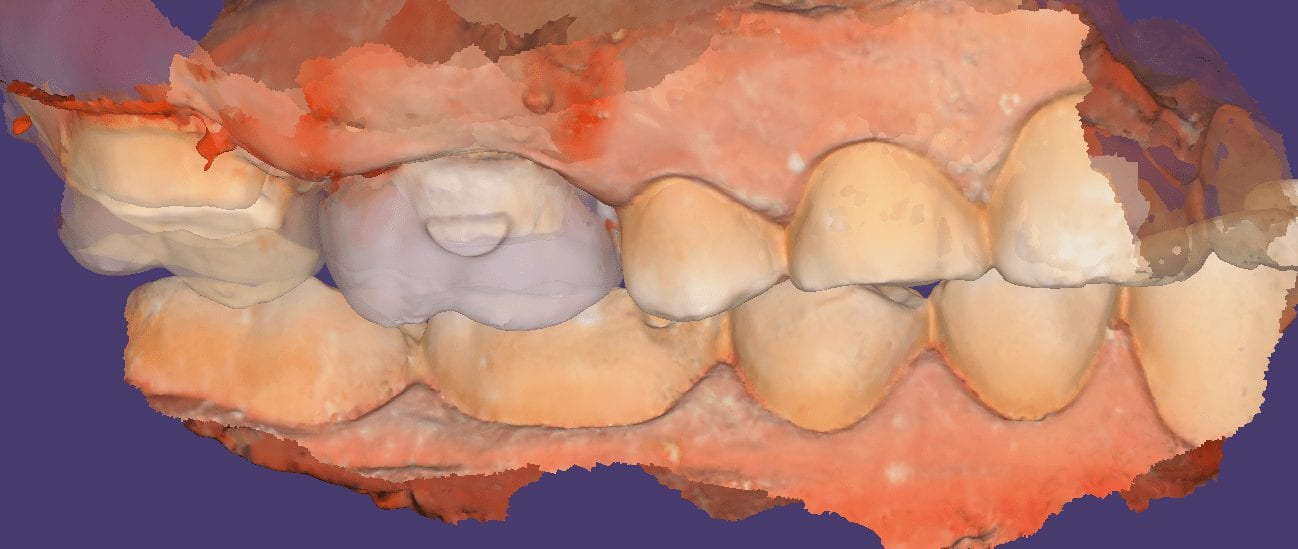

Local HD Scanning with Medit i500 Version 2.0

January 15, 2019A new feature coming soon to Medit I500 is localized High Definition Scanning. There are two modes you can scan and save the models in; Normal and High Definition. In […]

A new feature coming soon to Medit I500 is localized High Definition Scanning. There are two modes you can scan and save the models in; Normal and High Definition. In […]